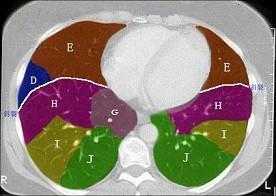

问题 结合肺段模式肺动脉干与右肺动脉层面肺动脉干与右肺动脉层面(见图), 心室层面(见图), 主动脉弓层面(见图), 左右心房层面(见图),选出左肺上叶的组成 ( )

选项 A、A+B+C+D+E B、A+B+C+D+E+F C、A+B+C D、A+B+C+D E、A+B

答案 A